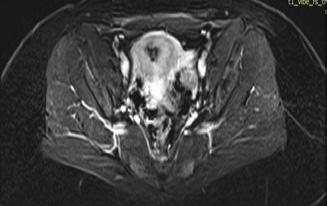

Figura 1. Pacient de 57ani cu simptomatologie acută sugestivă pentru AVC ischemic acut: CT -ul nativ nu a decelat elemente de semiologie sugestive pentru AVC ischemic acut (A), însă secvențele IRM au evidențiat o arie în hipersemnal FLAIR (B) și cu restricție de difuzie (C) localizată occipital paramedian dreapta, sugestivă pentru AVC ischemic acut (Spitalul Clinic de Urgență „Prof. N. Oblu“, Iași)

În contrast, imagistica prin rezonanță magnetică, în special secvențele de difuzie, oferă o sensibilitate superioară pentru detectarea precoce a infarctului ischemic,

fiind capabilă să identifice modificări la nivel celular la doar câteva minute după debutul simptomelor (Figura 1) (Mouridsen et al., 2020), (Nukovic et al., 2023). De asemenea, IRM este capabilă să ofere o evaluare superioară a integrității parenchimului cerebral, a viabilității țesutului și a extinderii leziunii ischemice, facilitând o caracterizare mai detaliată a AVC-ului ischemic (Cortés-Albornoz et al., 2025).